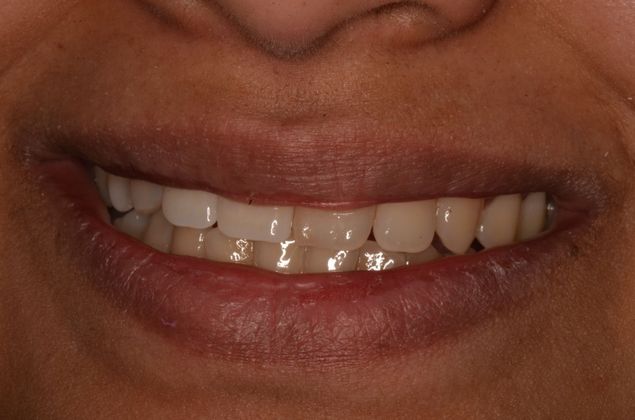

Two implants with crowns replacing infected root canals and old porcelain fused to metal crowns